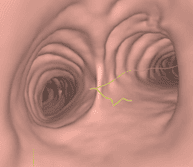

Mini-sonde endobronchique

De quoi s’agit-il ?

Cette technique nécessite un fibroscope bronchique, c’est-à-dire une caméra miniaturisée permettant d’explorer le poumon et les bronches de l’intérieur, par les voies naturelles.

La minisonde est une sonde de 2 mm qui s’insère dans le fibroscope permettant compte tenu de sa petite taille d’ aller plus loin dans les bronches de petit calibre. Cette minisonde est elle-même équipée d’une sonde d’échographie, miniaturisée à l’extrême, permettant d’examiner le poumon de l’intérieur.

A quoi ça sert ?

Ainsi des cancers à des stades plus précoces qu’auparavant peuvent être repérés et opérés.